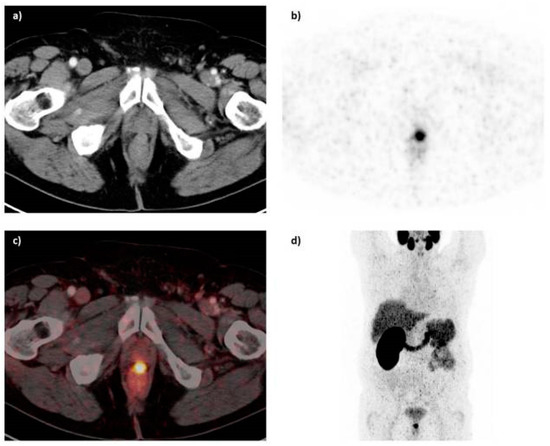

Figure 19.

68Ga-PSMA-11 PET/CT image of a patient with locally recurrent prostate cancer (PSA 3.7 ng/mL) after radical prostatectomy (SUVmax 12.4) who received 140 MBq of the 68Ga-labeled tracer molecule and was scanned at 1 h p.i.; (a) CT image; (b) PET image; (c) PET/CT fusion image; (d) MIP (Reprinted with permission of [145]).

The PSMA inhibitor PSMA-617 labeled with 68Ga was also clinically assessed in the diagnosis of prostate cancer by PET-CT [146]. 68Ga-PSMA-617 shows lesions of prostate cancer with high contrast, especially in late images (Figure 20). Maximum contrast of tumor lesions was achieved between 3 and 4 h after injection.

Figure 20.

(A–C) 68Ga-PSMA-617 PET/CT of a patient at 1 h after injection. Red arrows point to a bone metastasis with SUVmax of 21.7 at 1 h and 32.6 at 3 h after injection. (A) Low dose CT; (B) Fusion of PET and CT; (C) MIP of PET/CT. MIP = maximum-intensity projection (Reprinted with permission of [146]).